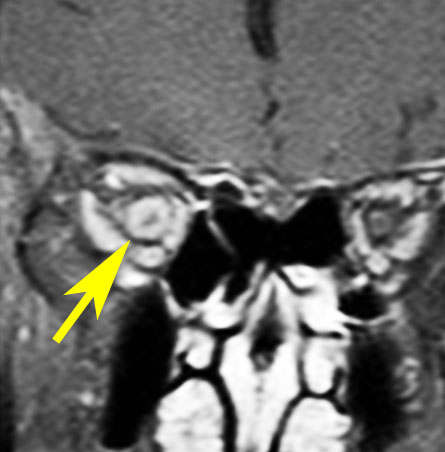

静脈洞交会髄膜腫 meningioma of the confluence of sinuses

若い女性に偶然発見されたものです。直静脈洞と静脈洞交会の接合部あたりに発生したもので,静脈洞はほぼ閉塞に近い所見でした。しかし,この部分の静脈洞は,テント硬静脈側副路が発達することがあるので,硬膜を含めた積極的な摘出をすることは絶対にできません。もしほんの少しでも流れがある直静脈洞を閉塞させると短時間に脳死になるような脳静脈圧亢進が生じる可能性があるからです。静脈洞内に少し取り残して(右下の矢印)手術を終了しました。手術後には定位放射線治療を行って再増大を防ぎます,